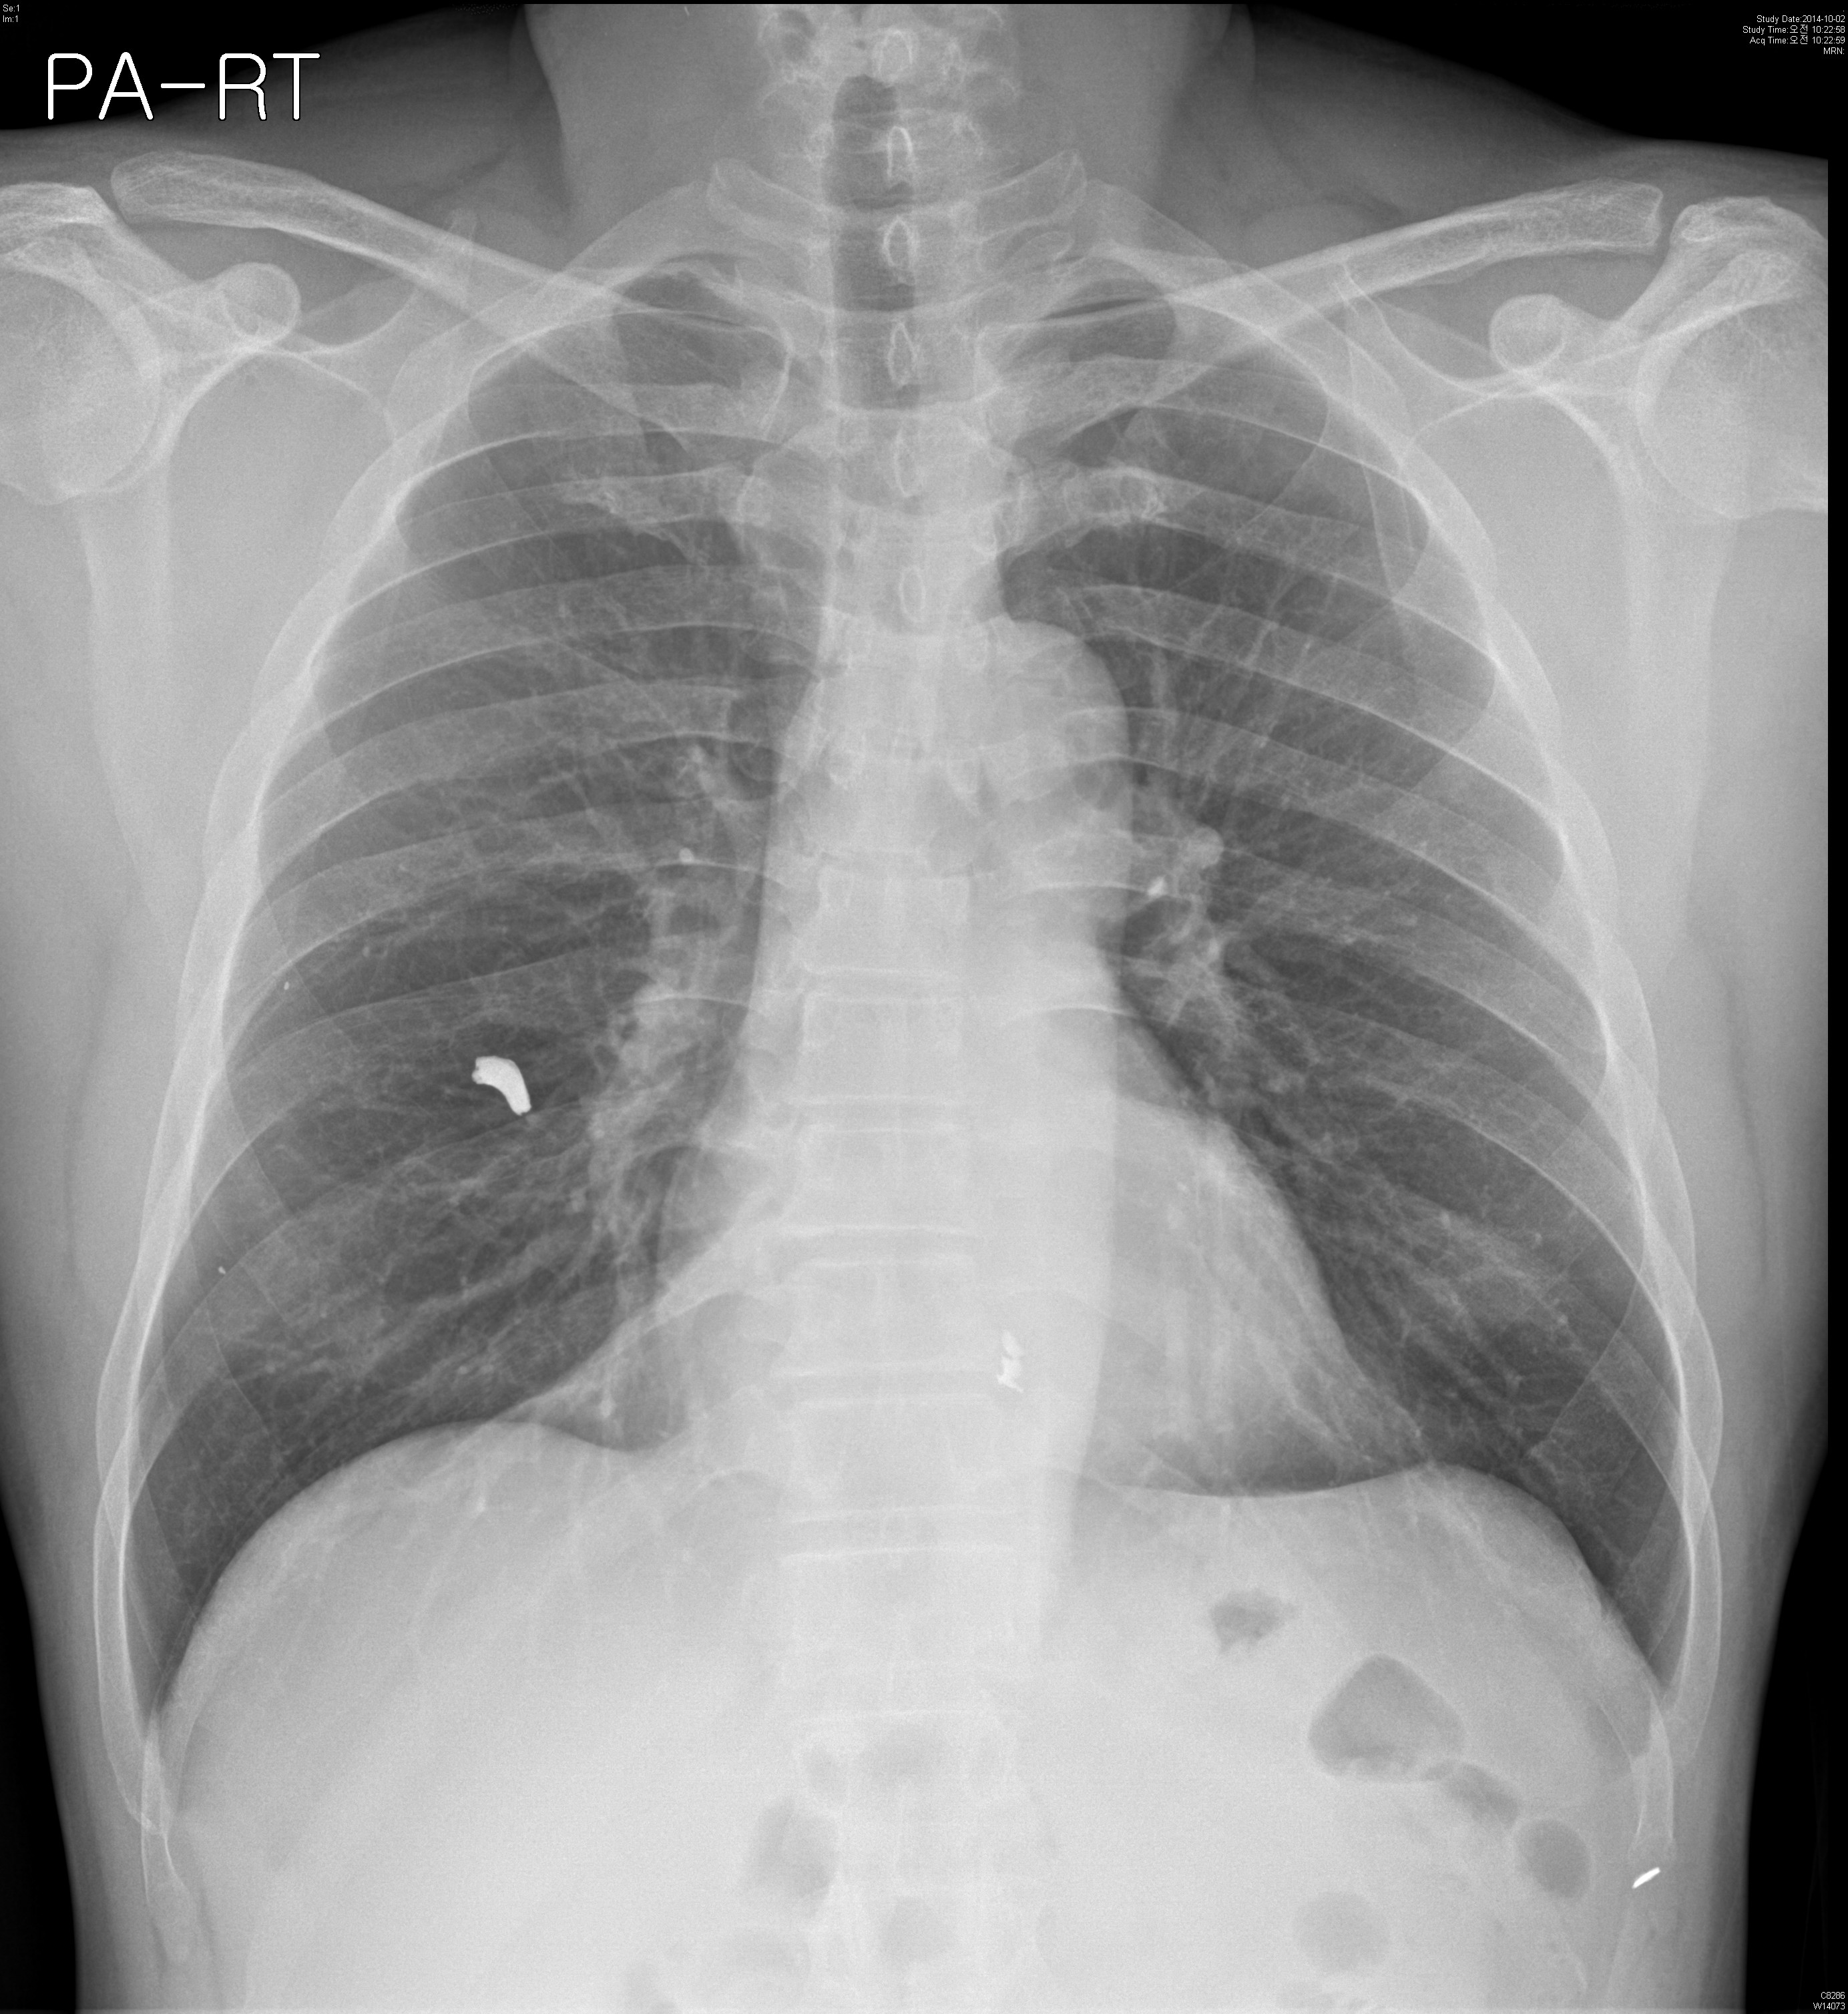

M/54, Abnormal CXR on Operability consult

¾È°ú¿¡¼­ ¼ö¼ú °èȹ Áß Chest PA »ó¿¡¼­ ¹ß°ßµÈ calcification À¸·Î ½ÃÇàÇÑ Chest CT ÀÔ´Ï´Ù.

È£Èí±â Áõ»óÀº ¾ø¾úÀ¸¸ç, ÀÌÀü ±º´ë¿¡¼­ ÆøÅºÀ» ¸ÂÀº °ú°Å·ÂÀÌ ÀÖ½À´Ï´Ù.